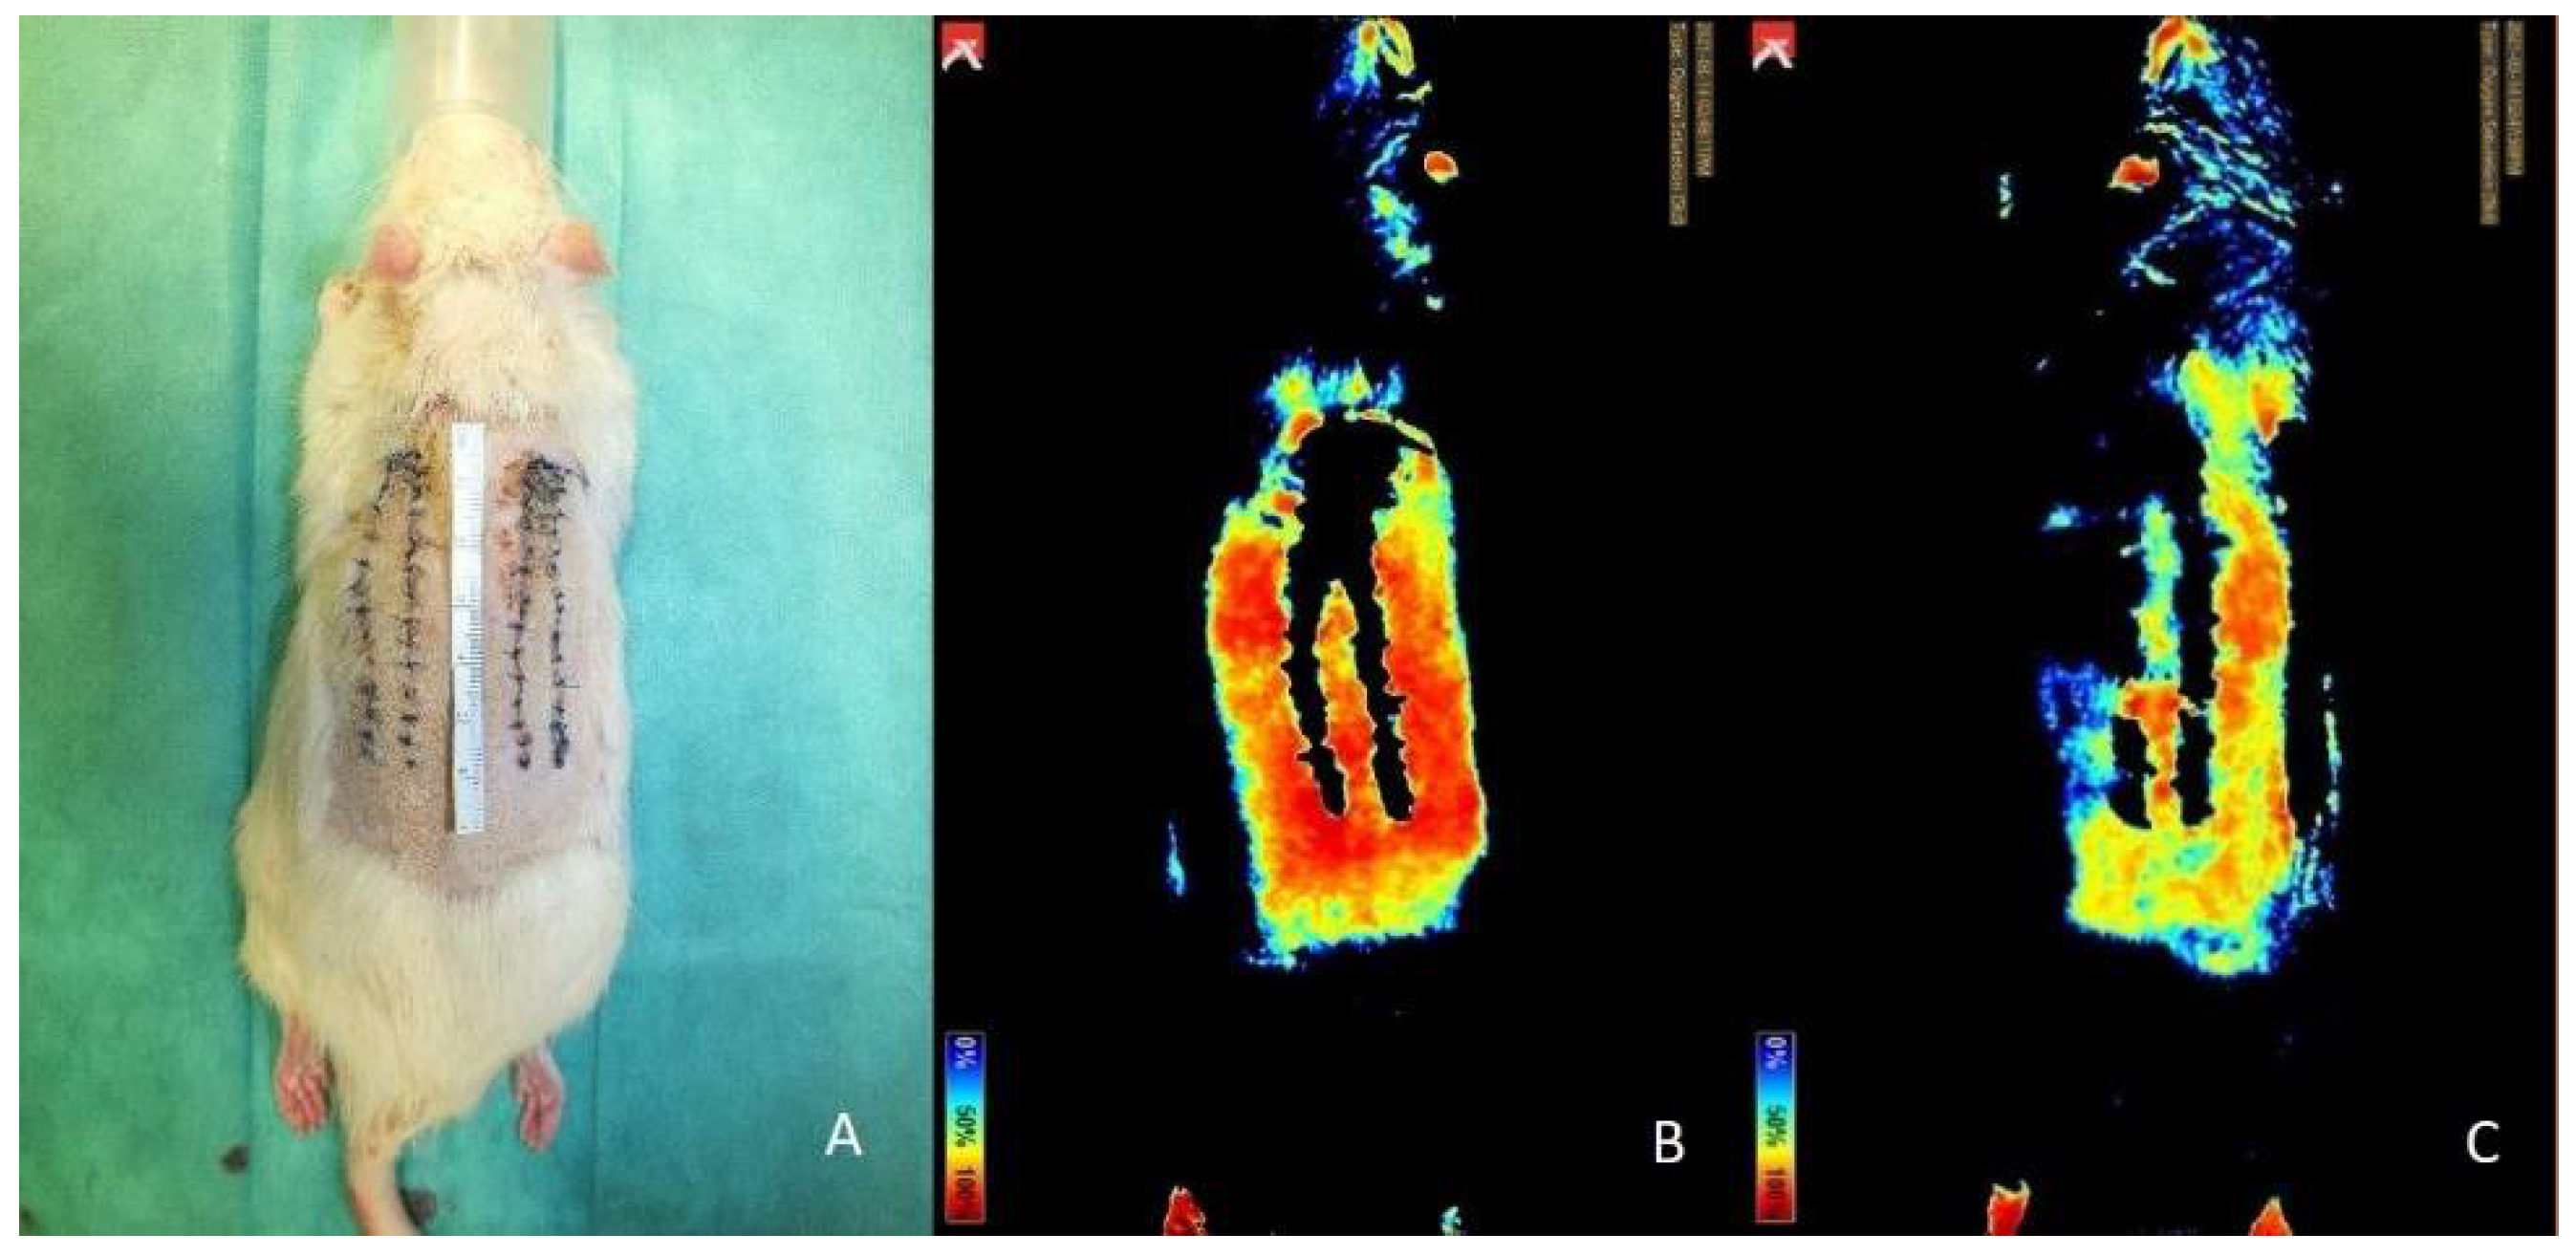

3.5. Near-Infrared Reflectance-Based Imaging and Infrared Thermography